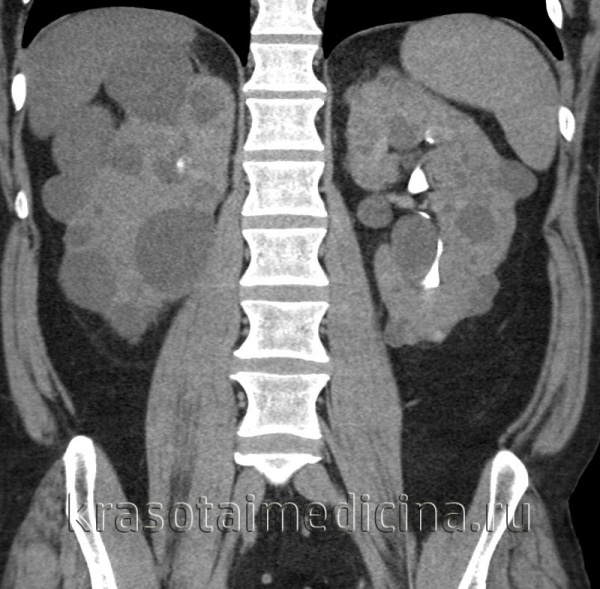

При УЗИ почки резко увеличены, но форма их сохранена. Паренхима имеет повышенную эхогенность, крупнозернистая, с наличием мелких эхонегативных зон («соль с перцем»). На более поздней стадии помимо веретенообразных могут появиться кисты сферической формы. УЗИ печени выявляет повышенную эхогенность, а позднее — хорошо различимые кисты желчных протоков.

Диагностике помогают данные КТ и МРТ почек и печени и экскреторной урографии.

Диагностика аутосомно-рецессивного поликистоза почек. Пальпируемое двустороннее объемное образования в боковых отделах живота у грудного ребенка с гипоплазией легких, маловодием и артериальной гипертонией в отсутствие поликистоза почек у родителей позволяет диагностировать болезнь. При УЗИ почки обычно резко увеличены и равномерно повышена их эхогенность со стертостью границы между корковым и мозговым веществом. Диагноз подтверждают также клинические и лабораторные признаки фиброза печени, патологические изменения желчных протоков в биоптате печени, наличие поликистоза почек у сиблингов или близкое родство родителей. Аутосомно-рецессивный поликистоз почек следует отличать от увеличения почек при поликистозной дисплазии, гидронефроза, опухоли Вильмса и двустороннем тромбозе почечных вен. В семьях хотя бы с одним больным ребенком возможна пренатальная диагностика с помощью анализа генетического сцепления и использования информативных маркеров.